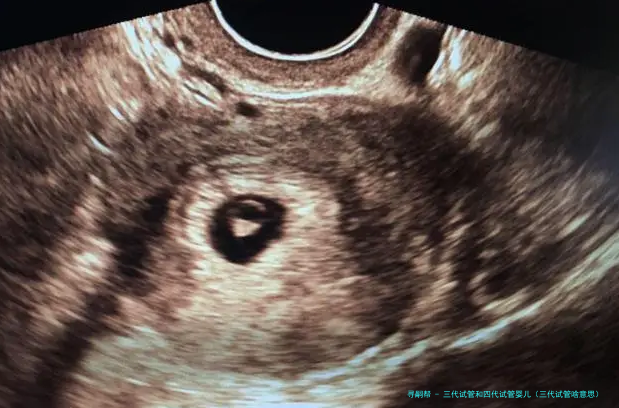

试管婴儿的医学术语称:胚胎转移技术-胚胎移植,其过程是女的一方先使用药物促排卵,再从卵巢内拿出卵子,男方拿出精子,在实验室将精子、卵子结合培育成胚胎,然后又将胚胎转至子宫腔内,令其着床、妊娠。

试管婴儿即是采用人工方法让卵细胞体体和精子在试管受孕,并进行初期胚胎生长,然后移植到本人体内人宫内发育而降生的婴儿。

“试管婴儿”的完整名称叫做“试管受孕和胚胎移植术”(试管婴儿(IVF)-ET),是一种今世诊疗技术。原理是将卵子、精子分别拿出体外,在人工受控制条件下完成精卵结合,成活后再受精卵移植到母亲身内,着床发育。

试管婴儿道理 “试管婴儿”其实不是真正在试管里长大的婴儿,而是从卵巢内拿出若干个卵子,在实践室里使之们与男方的精子结合,形成胚胎,然后挪动转移胚胎到子宫内,让它位于妈妈的子宫内着床、妊娠。